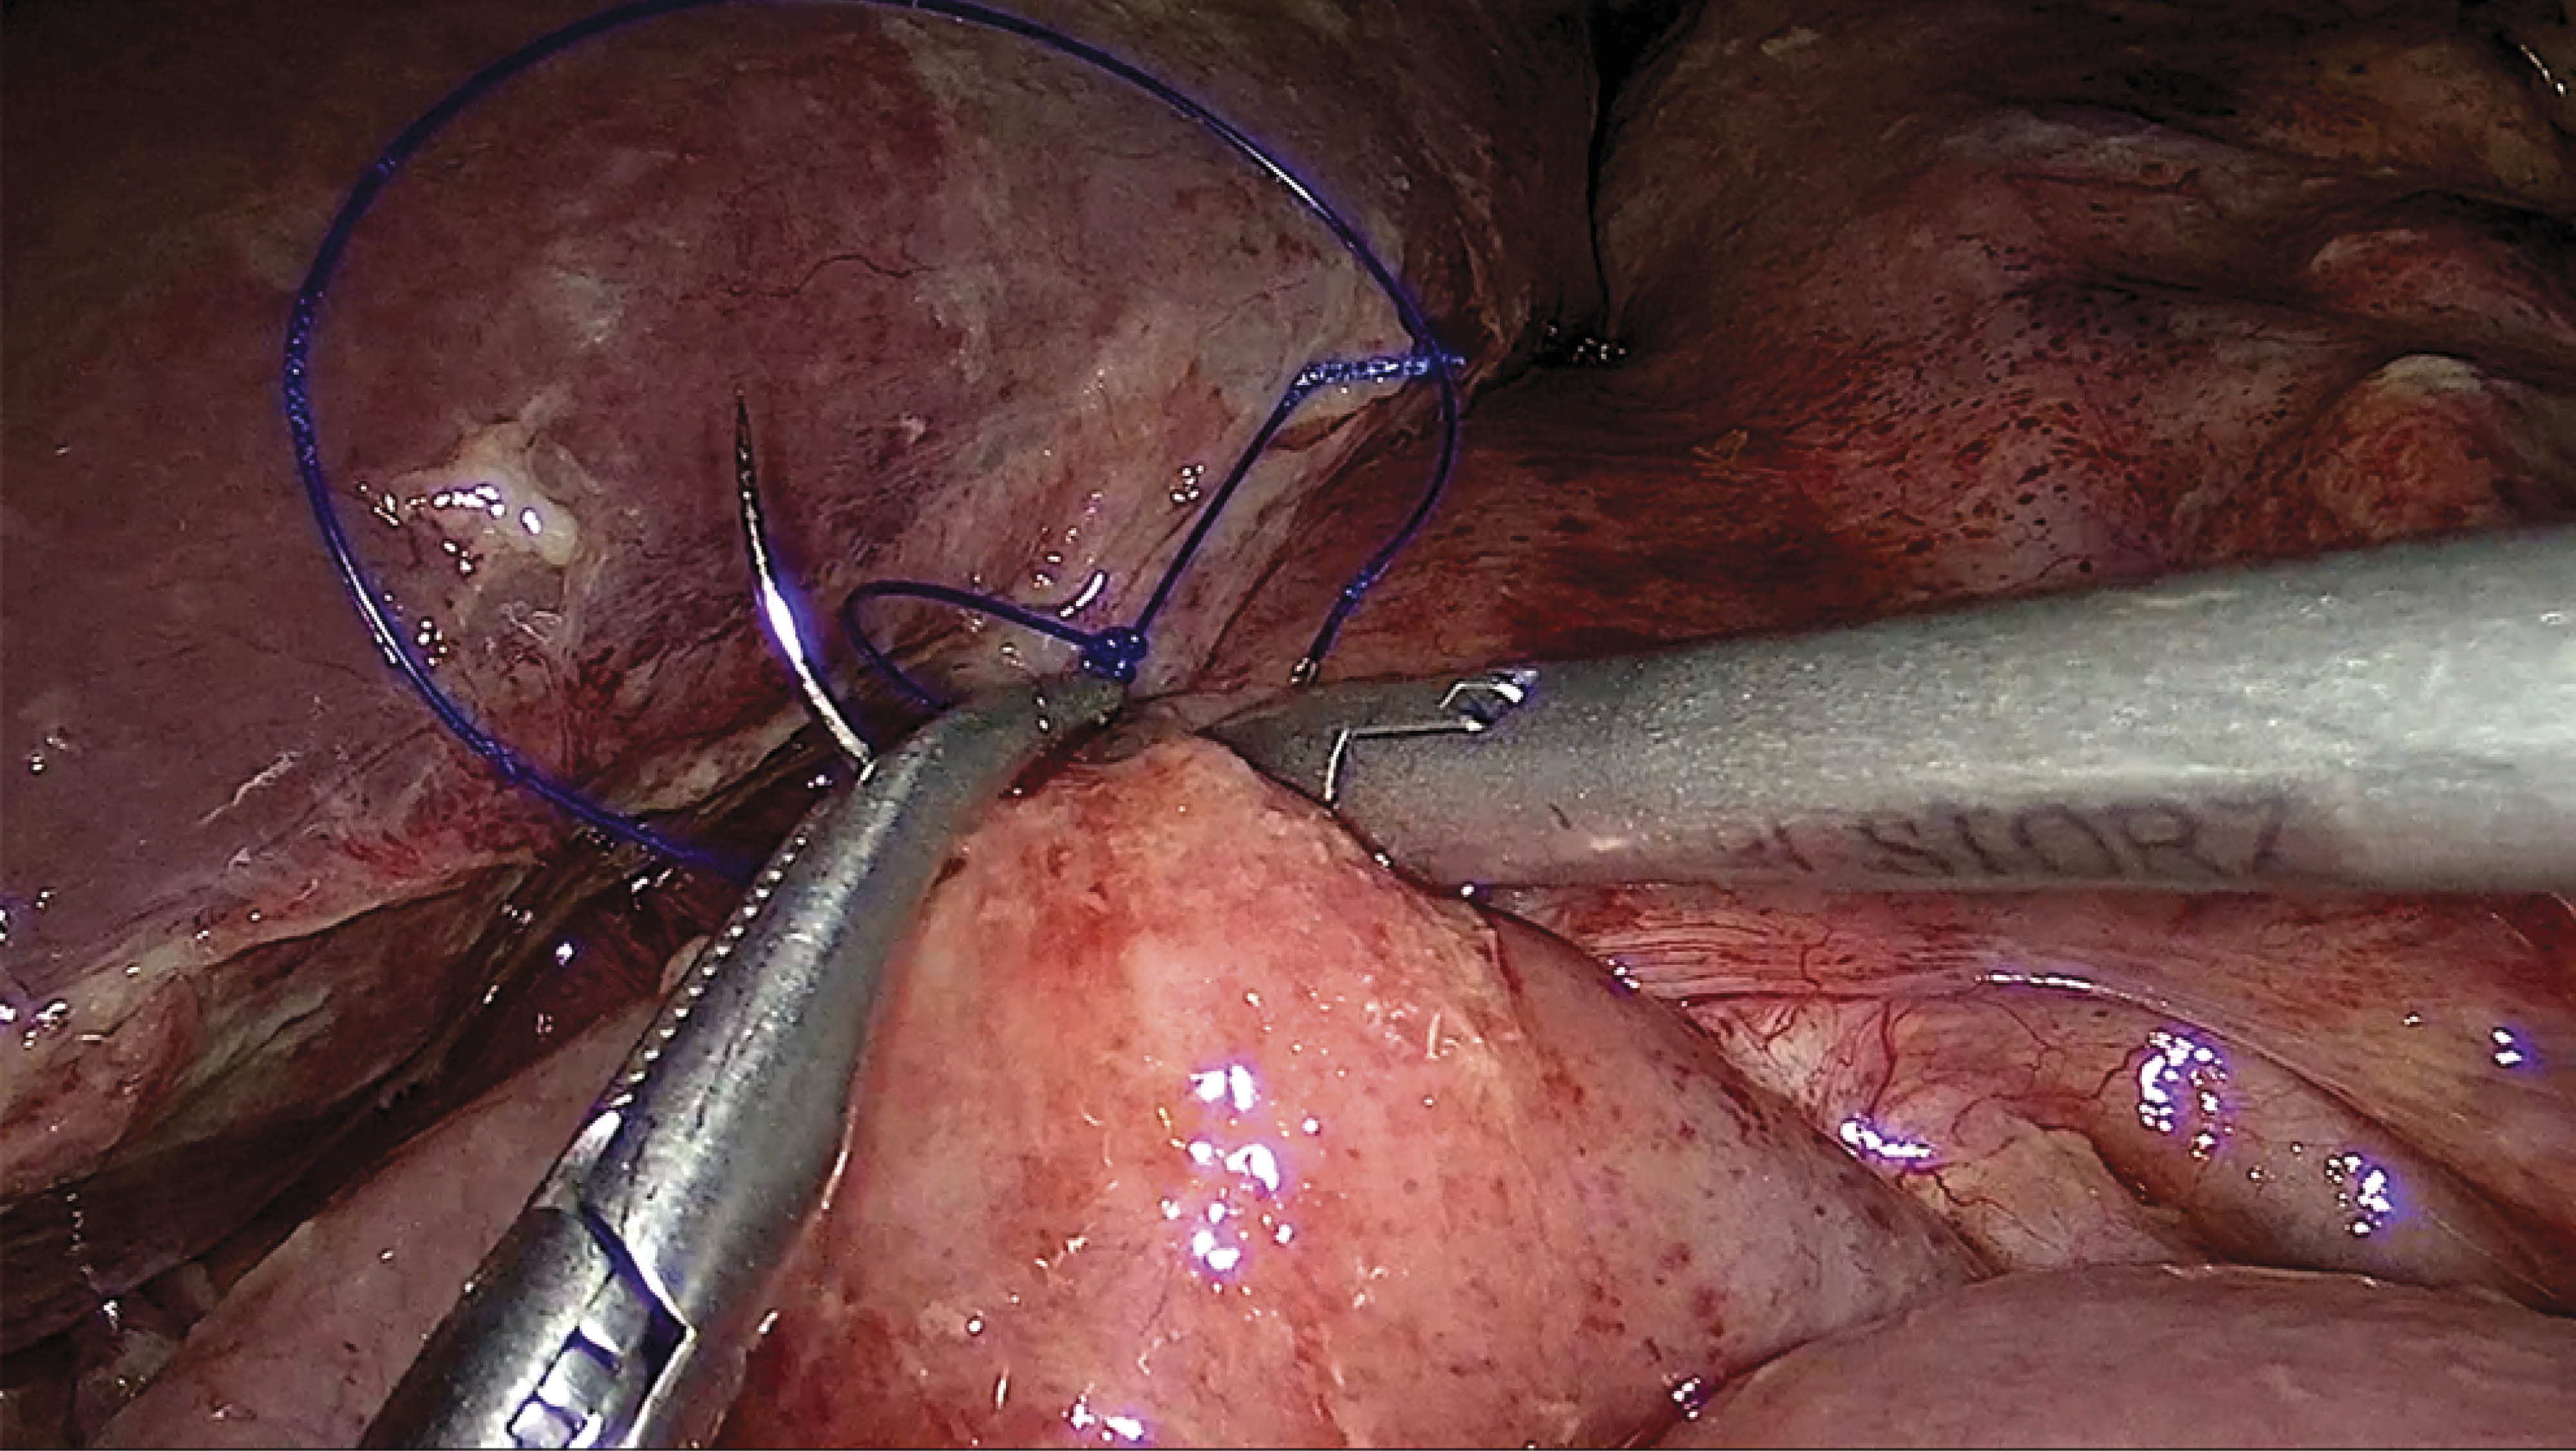

Management of late perforation of non-marginal jejunal ulcer in Roux-en-Y bypass patient

Peptic ulcer formation, while common in the stomach and duodenum, are rarely seen in the jejunum. Margin ulcer formation is the most frequent cause of jejunal perforation in patients with Roux-en-Y gastric bypass (RYGB). Non marginal jejunal ulcer perforation is an extremely rare condition. We present a case of a non-marginal late jejunal ulcer perforation in a patient with RYGB.

Figure 1